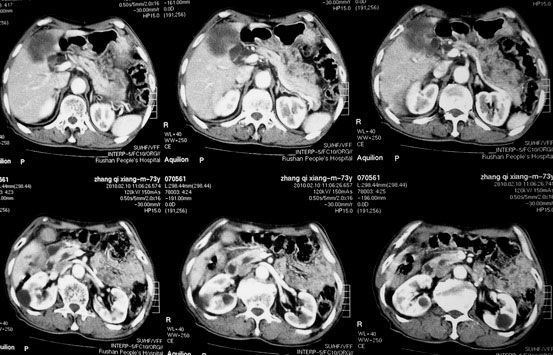

肝胆管细胞癌

患者AFP正常,无肝病病史。CA199 1000ng/ml,CEA偏高。血象WBC正常,N偏高。

化脓性胆囊炎累及肝脏;胆管细胞癌;肝转移瘤

活检病理

:是

胆管细胞癌

。

这个病人开始就是主要鉴别的肝脓肿和胆管细胞癌。可是增强后环征也不明显,占位内造影也非常不明显。这种情况怎么判断?谢谢大家。

病灶强化幅度较轻,低密度坏死区内见无定形高密度影,是其特点。